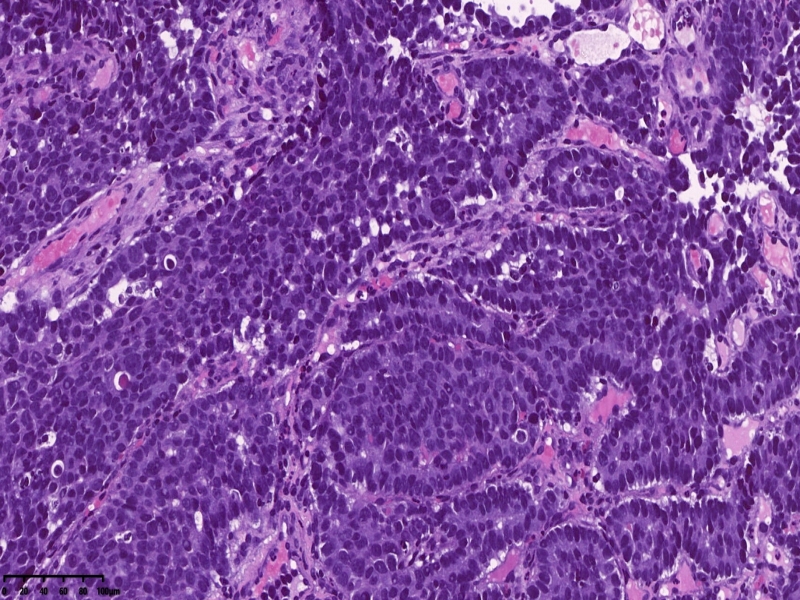

镜下所见:胃粘膜组织数块,炎症背景,其中3块固有层内可见细胞团,瘤细胞排列呈条索状迂回后呈巢状,巢的边缘瘤细胞呈栅栏状。细胞形态似柱状。

第一感觉考虑神经内分泌肿瘤?会诊考虑低分化腺癌。以前也遇到一个类似病例,贲门口占位,初步考虑神经内分泌肿瘤,但是神经内分泌标记均为阴性,最后考虑低分化腺癌。